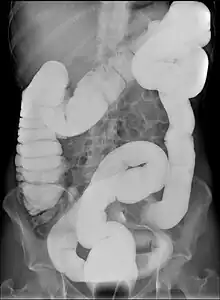

Dolichocolon

Dolichocolon is an abnormally long large intestine.[1] It should not be confused with an abnormally wide large intestine, which is called a megacolon.

Dolichocolon may predispose to abnormal rotation (see volvulus) and interposition between the diaphragm and the liver (see Chilaiditi syndrome). It is more commonly seen in the elderly, some psychiatric patients or in institutionalised individuals. It is not, however, a part of normal aging. The exact cause remains unknown. Dolichocolon is often an incidental finding on abdominal X-rays or colonoscopy. It is not by itself a disease and as such requires no treatment. The term is from ancient Greek dolichos, the long distance in running, and colon.